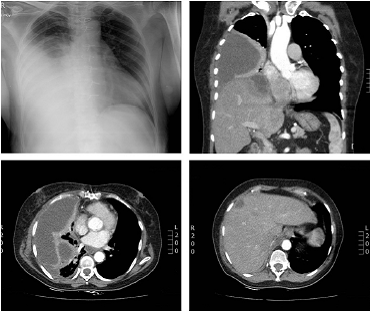

Con el diagnóstico inicial de derrame pleural secundario a neumonía bacteriana se manejó con antibioticoterapia (cefepime y claritromicina). Previamente a la toracentesis diagnóstica se realizó una tomografía computarizada de tórax (fig. 1 ).

Figura 1 Radiografía y tomografía computarizada de tórax (reconstrucciones axial y coronal). Colección pleural derecha lateral y basal, con atelectasia pasiva del parénquima pulmonar adyacente. Lesiones focales en el parénquima hepático con colección subcapsular en contacto con el diafragma que realza con el medio de contraste.

La presencia en la tomografía de colecciones pleurales y lesiones focales hepáticas indicó el diagnóstico de absceso hepático bacteriano drenado a la cavidad pleural. El Servicio de Cirugía General decidió realizar el abordaje quirúrgico de las colecciones. En cirugía se encontraron abscesos hepáticos (2) en los segmentos viii y iva con 800 cc de pus, una perforación diafragmática de 3 cm y 1.000 cc de pus en la cavidad pleural derecha. Los abscesos hepáticos fueron drenados y se realizó decorticación pleural derecha. Durante la cirugía presentó sangrado que requirió transfusión de hemoderivados, soporte hemodinámico y ventilación mecánica durante 5 días en la Unidad de Cuidado Intensivo.